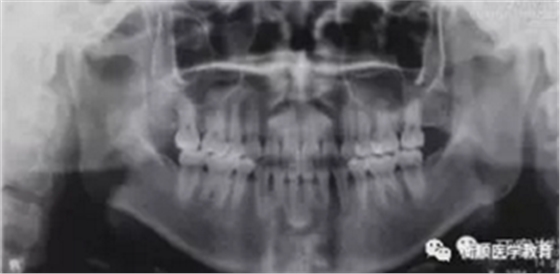

图3 治疗前曲面体层片